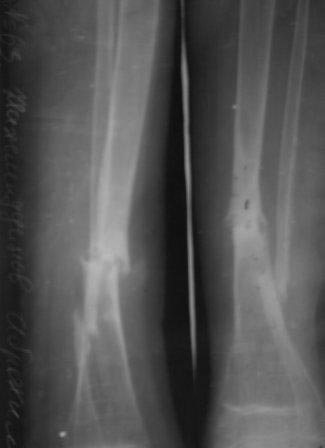

Уважаемые коллеги! помогите советом! Мальчик 2000 г.р. В 2007г получил

перелом н/з костей правой голени,

в районе лечили гипсом 6 месяцев, сращения нет, в обл.центре КДО

аппаратом Илизарова - 3 месяца, после повторная деформация, в НИИТО КДО

аппаратом Илизарова -7 месяцев, перелом якобы сросся, но после снятия

аппарата через 2 недели после незначительной травмы повторный перелом. И

нога сильно атрофировалась.(Мне кажется у ребенка был врожд. ложный

сустав, латентная форма) , и в 2011 г, в октябре обратились к нам. ,

выписали, повторно приехали только ч-з 1,5 года вот с такой деформацией,

но ребенок ходит в школу, бегает, незначительно хромает, родители

требуют исправить деформацию.